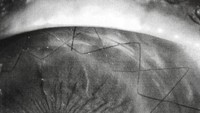

Jahitan yang rapi seolah-olah jadi penghias mata membentuk pola yang cantik. (Foto: Internet)

Seberapa kompleks jahitan tergantung dari keterampilan tangan sang dokter tentunya. (Foto: Internet)